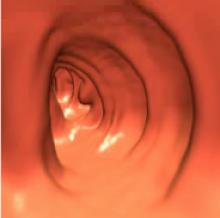

May 8, 2009 - The debate heats up amongst doctors in the advent of the Centers for Medicare & Medicaid Services (CMS) decision on reimbursement for virtual colonoscopy (also known as CT colonography or CTC).